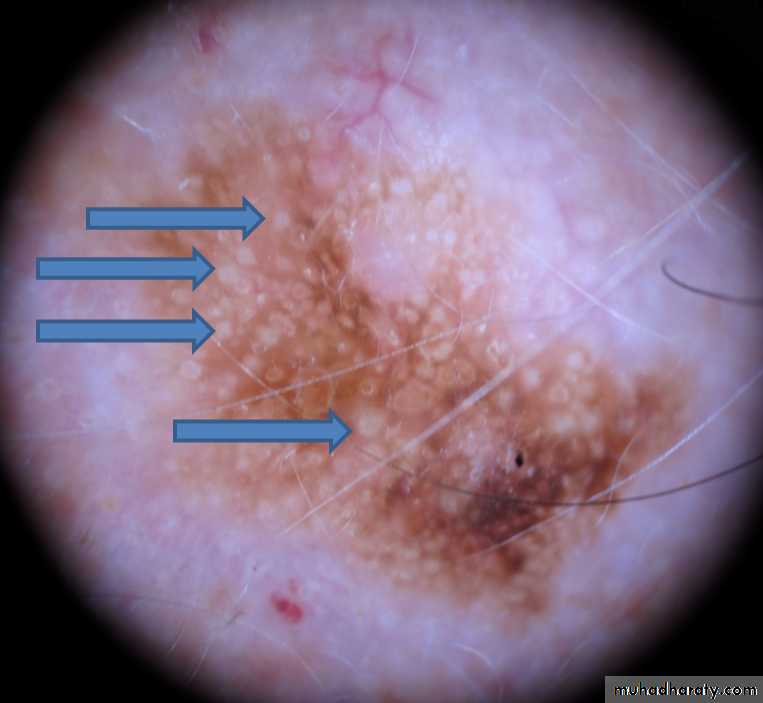

Use dermoscopy to look for keratin pseudocysts.

These are small white spots commonly found in seborrheic keratoses.

clinical white spots are directly comparable with the horn pseudocysts which is it histological equivalent.

Dermoscopy of SKs showing horny pseudocysts